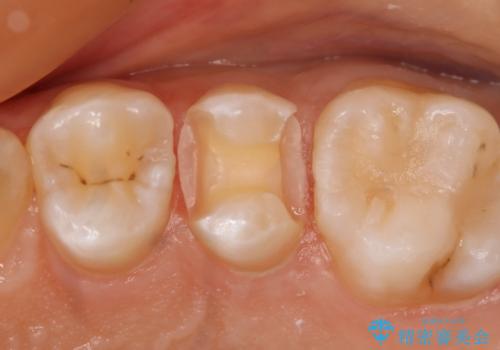

- 左上5番の虫歯治療を主訴に来院された患者様です。

セラミックでの治療を希望されたので形態・切削量を考慮しセラミックインレーでの治療を選択しました。

隣り合っている面(隣接面)は清掃がしづらく虫歯になりやすい場所です。

また、形態の再現が難しいのでインレーなどの補綴物での治療が第一選択となることが多いです。